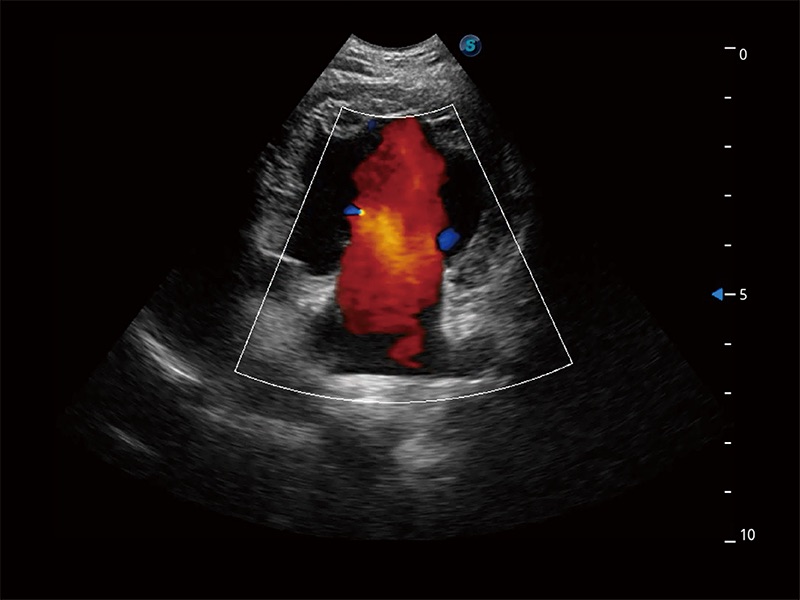

ProPet 80 配备了丰富的心脏探头群、先进的成像技术和专业的心脏测量工具,可帮助动物医生为不同体型和生理结构的动物提供心脏和心肌功能的全面评估。

通过360度任意调节3条M型取样线,在同一心动周期上观察心脏不同位置的运动曲线,得到准确的心功能测量数据,有效评估心肌运动及左心室功能。